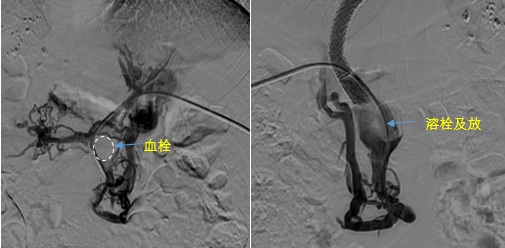

“我們來(lái)這兒,就是想解決大肚子的問(wèn)題,還有出血的問(wèn)題,我們前前后后因?yàn)槌鲅呀?jīng)做了7次內(nèi)鏡下治療,現(xiàn)在肚子很大,吃藥也沒(méi)用,飯也吃不好,覺(jué)也睡不好…….”在消化病醫(yī)院的診室里,患者馬阿姨一邊向醫(yī)生訴說(shuō)病情,一邊拍拍自己的肚子……